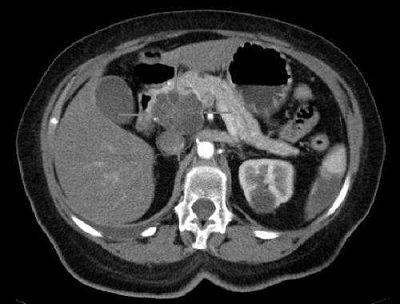

(图片来源: University of Caen)

对此,来自法国的研究者们对26名患者进行TMS治疗试验,另外还有33名健康人作为对照。MRI观察结果显示磁脉冲刺激的主要部位位于负责语言的大脑区域。经过两周的治疗,研究者们对患者的症状进行的重新评估。结果显示,这种疗法能够显著地缓解患者的幻听症状(34.6%),而对照处理的话则没有明显区别(9.1%)。